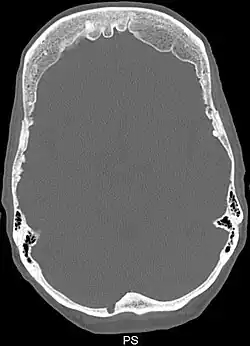

Zespół Morgagniego-Stewarta-Morela (ang. Morgagni-Stewart-Morel syndrome, Morgagni’s trias, łac. hyperostosis frontalis interna) – rzadka choroba genetyczna, która charakteryzuje się trzema głównymi objawami: 1) przerostem wewnętrznej powierzchni kości czołowej, 2) otyłością i 3) wirylizmem i hirsutyzmem[1].

- przerost wewnętrznej powierzchni kości czołowej (hyperostosis frontalis interna)